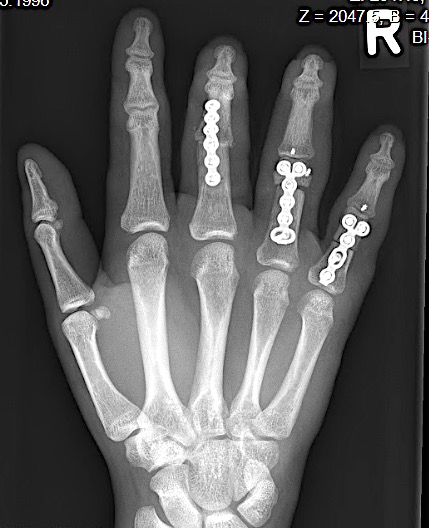

Case 1:

A 64-year-old male suffered a multi-fragmentary fracture of his right thumb metacarpal (Fig 1). An adapted 12-hole strut plate from the variable angle locking hand system was the implant of choice for fixation (Figs 2 - 4).

The strut plate provided good stability in a comminuted extraaricular fracture pattern and enables immediate mobilization. Bone callus formation was not witnessed during the healing process.